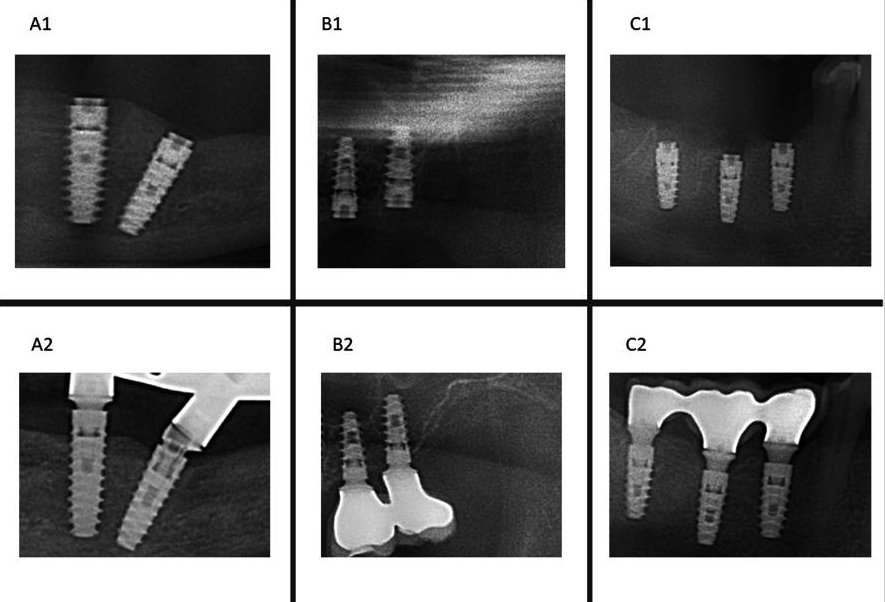

A BL example in IDI #33 (A1: March 2019- A2: September 2023); B BR example in IDI #26 (B1: November 2019- B2: January 2020); C BO example in IDI #46 (C1: January 2019-C2 January 2020)

This study concluded:

The present study supports the clinical efficacy of immediate implant placement protocol with high survival rates and acceptable MBL. Regarding the latter, the insertion of implants bone level about 3 mm infracrestal should be considered to ensure a subcrestal implant platform position during bone remodeling during the first months after implantation. The insertion of immediate implants in the jaw compared to the maxilla, the abutment height and rotational abutments demonstrated a positive impact over the MBL.